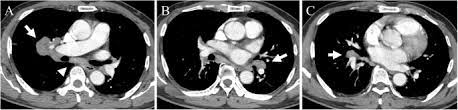

Can Lung Cancer Be Mistaken For Sarcoidosis - Case Report Pulmonary And Liver Sarcoidosis F1000research - Researchers emphasize that clinicians should be aware of systemic sarcoidosis because it can easily be mistaken for cancer progression.. Therefore we suggest that no lesion should be missed in these patients without biopsy by assuming lung involvement of sarcoidosis. Lung cancer should be excluded to confirm a diagnosis of sarcoidosis 4 , although the concurrence of sarcoidosis and lung cancer has been reported 5, 6, 7, 8 . Sarcoidosis patients may be misdiagnosed with tuberculosis, lymphoma, or lung cancer 4 . The standardized mortality rate for lung cancer was 3.26 (5.56 for males and 3.03 for females), indicating that sarcoidosis could be a risk factor for lung cancer. Various organs can be affected including the skin, lymph nodes, and liver.

When sarcoidosis affects the lungs, symptoms can mimic idiopathic pulmonary fibrosis including shortness of breath and a dry cough. Because both mesothelioma and sarcoidosis are hard to detect and present generalized chest and respiratory symptoms, the two conditions can be mistaken for one another. By definition, sarcoidosis is a systemic disease, affecting multiple organs in the body. If it is sarcoid, then you can get the help you need for this condition. There are currently no formal recommendations to guide the differential diagnosis workup between the evolution of lymphoma or a solid cancer and a granulomatous reaction associated with neoplasia. Since sarcoidosis and lung cancer can be present concurrently, performing biopsy to obtain pathology results from any suspected lung lesion in a patient diagnosed with sarcoidosis is essential. What every physician needs to know. Sarcoidosis is known to be a cancer mimicking and masking condition, it can follow cancer or develop concurrently with cancer, and significantly increased risk of cancer can affect sufferers of sarcoidosis.

That same fungal infection is often frequently mistaken for squamous cell carcinoma, or skin cancer, when it shows up on the skin. Sarcoidosis is a rare disease caused by inflammation. It usually occurs in the lungs and lymph nodes, but it can occur in almost any organ. Only 10 similar cases had been reported previously. When sarcoidosis affects the lungs, symptoms can mimic idiopathic pulmonary fibrosis including shortness of breath and a dry cough. No prior imaging was available for comparison. After some conversations and research i now know sarcoidosis can be mistaken for cancer. A condition called sarcoidosis, most commonly found in the lungs, can be mistaken for cancer, tuberculosis, or other infections, as its symptoms are similar. That time between when they tell you the possibilities and when you get the results from the biopsy is terrifying. Occasionally this pattern of fibrocystic change is seen in the lower lung zones, an atypical location that may cause pulmonary sarcoidosis to be mistaken for. Which was a flare up of sarcoidosis. A permanent pathological slide, however, indicated that right interlobar (#11s) lymph nodes involved both sarcoidosis and lung cancer metastasis. Can sarcoidosis turn into cancer.

Pancreatic cancer may also be misdiagnosed as gallstones or pancreatitis, or the inflammation of the pancreas. After some conversations and research i now know sarcoidosis can be mistaken for cancer. A condition called sarcoidosis, most commonly found in the lungs, can be mistaken for cancer, tuberculosis, or other infections, as its symptoms are similar. I've been going to support groups for the disease for 20 years now and find 3 or 4 patients a year who are diagnosed initially as having lung cancer. That same fungal infection is often frequently mistaken for squamous cell carcinoma, or skin cancer, when it shows up on the skin. Sarcoidosis can also affect calcium metabolism, the nervous system, the liver and spleen, muscles, bones and joints, the kidneys, lymph nodes, or any other organ. Various organs can be affected including the skin, lymph nodes, and liver. Sarcoidosis and neoplasia, especially lymphoma, can show overlapping presentations, thus making the diagnosis and treatment harder to deal with. Copd is a term used for a group of obstructive lung diseases. There are currently no formal recommendations to guide the differential diagnosis workup between the evolution of lymphoma or a solid cancer and a granulomatous reaction associated with neoplasia. Since sarcoidosis and lung cancer can be present concurrently, performing biopsy to obtain pathology results from any suspected lung lesion in a patient diagnosed with sarcoidosis is essential. Despite careful preparation, it thus remains difficult to distinguish between these conditions even when lymph nodes are strictly evaluated. Only 10 similar cases had been reported previously.